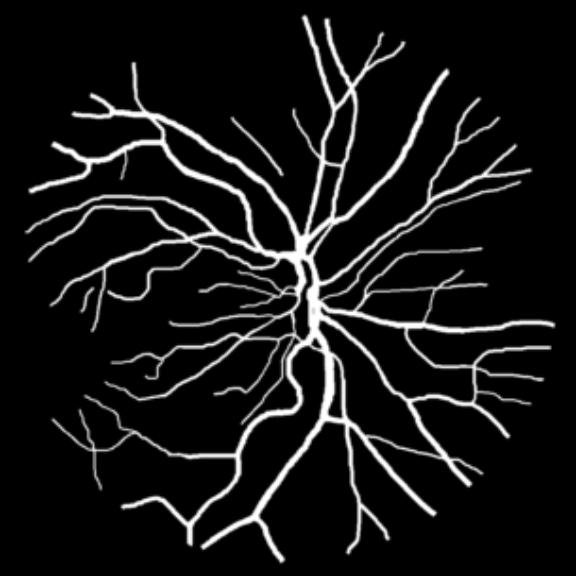

We perform retina blood vessel segmentation experiments on two different datasets, DRIVE[25] and CHASE_DB1[26]. DRIVE dataset consists of 40 retinal images in total, in which 20 samples are used for training and remaining 20 for testing. The size of each original image is 565584 pixels and all images are cropped and padded with zeros to 576576 to get a square dataset. We randomly select 531265 patches whose size is 4848 from 20 of the training images in DRIVE dataset and 10 of them are used for validation. Another dataset, CHASE_DB1, contains 28 color retina images with the size of 999960 pixels which are collected from both left and right eyes of 14 school children. 20 samples are randomly selected as training set and the remaining 8 samples are used for testing. Similar to DRIVE dataset, we crop all the samples into 960960 pixels and randomly select 412400 patches of 4848 pixels from the training set of which 10 are used for validation and the remaining for training.

All three datasets are processed by subtracting the mean and normalizing according to the standard deviation. We use Adam optimizer, set the initial learning rate to 0.001 which is reduced by ten times if the training set loss does not drop during 10 consecutive epochs. We augment data using rotation, crop, flip, shift, change in contrast, brightness and hue. We set batch size to 4 for Skin Dataset and 32 for DRIVE and CHASE_DB1 whose patch size is relatively smaller. For each model we train 50 epochs and the result is shown in Table 1. Models with MixModule have better performance than those not and the best performance in each metric all comes from MixModule-based models. We also show some outputs of the networks in Figure 4.